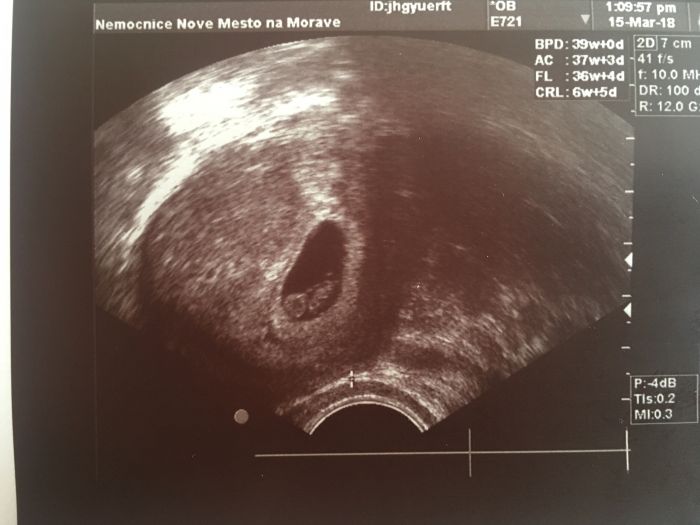

tak se tez pochlubim